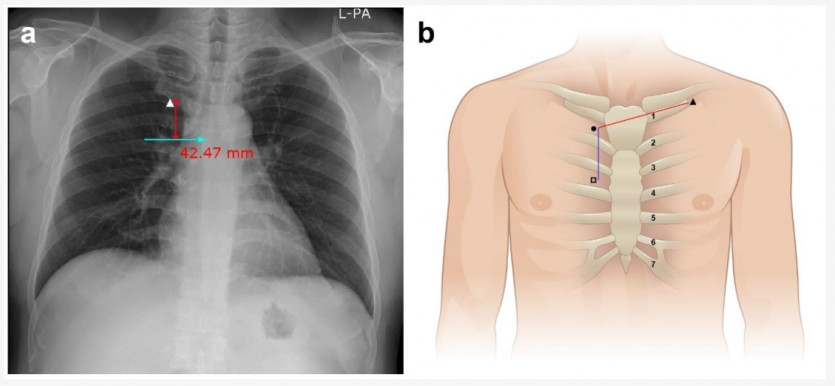

Many prefer to position the catheter tip within the

proximal right atrium. This location results in improved flows, less

recirculation, less acute failures and better catheter patency

주입용: 3rd

투석용: 4th ICS

Anterolateral puncture of the right internal jugular vein